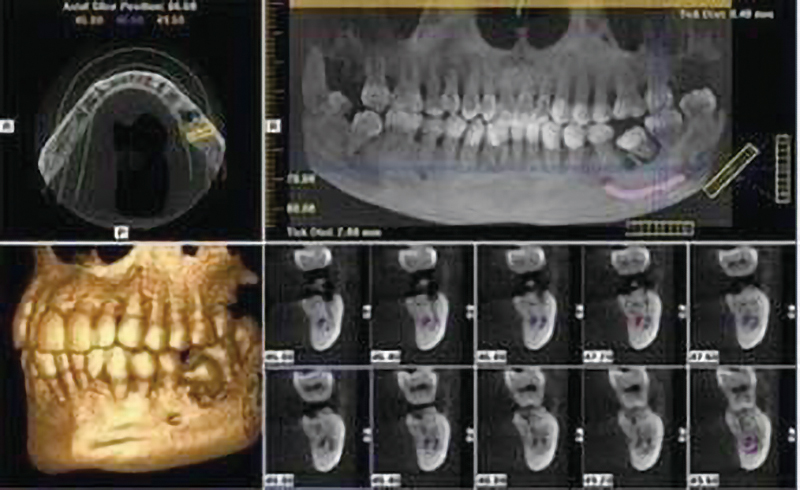

各分野の専門医による高度な歯科治療

ひとりの医師が複数の治療を行う日本とは異なり、タイでは専門医制をとるのが一般的。総合歯科である同医院にも、補綴(ほてつ)歯科・歯周病科・口腔外科・小児歯科といった各治療分野のエキスパートたちが在籍し、より高度な治療を受けることができます。

「インプラント(デンタルインプラント)」とは、虫歯や事故などで失ってしまった歯を人工歯根を埋め込み補う歯科治療のこと。同医院では世界トップ3のシェアを誇るスイス・ストローマン社制のインプラントを使用し、日本帰国後の治療・メンテナンスもスムーズ。

歯並びを治すための歯列矯正は、一般的に金属が目立つワイヤー矯正よりも、「インビザライン」と呼ばれる透明なマウスピースを装着する治療方法が人気のよう。3Dスキャニングシステム「iTero」を導入し、歯の型取りが不要なのも嬉しいポイントです。